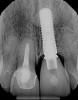

Figure 8 shows the provisionalization of No. 8 at 6 weeks postoperatively and a screw-retained provisional restoration on No. 9 to develop the subgingival transitional zone (key Nos. 8 through 10). The transitional zone will be duplicated using the custom impression coping technique. Figure 9 and Figure 10 depict the completed crowns at 5 years; implant No. 9 was screw-retained (key No. 10). In Figure 10 note the convex contours facial to implant No. 9 that are attributed to the connective tissue grafting as part of the surgical protocol creating biotype conversion from a thick to a thicker biotype. Figure 11 through Figure 13 show 5-year postoperative patient smile, periapical x-ray, and CBCT, respectively.

Fig 12. Periapical radiograph at 5 years.

Figure 12

Fig 13. Site-specific CBCT at 5 years with a measured 2.5-mm bone width facial to the implant.

Figure 13